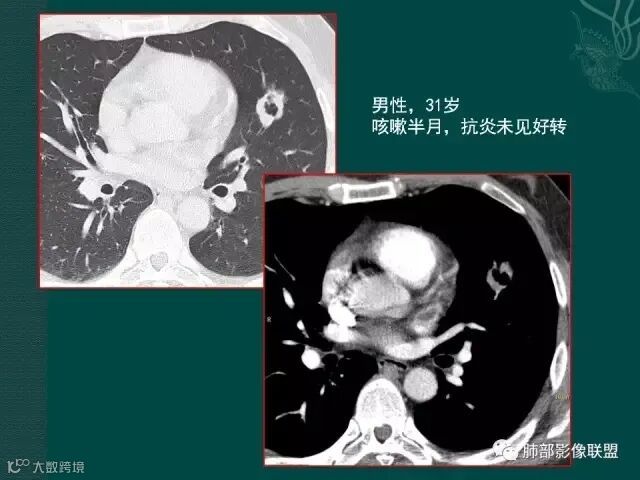

病史似乎是炎性;空洞型病变,靠近纵隔的时候,一定要看对纵隔是否有侵蚀,这是相当重要的。

红箭头所指是右上肺静脉,起始部是完好的,上一层被病变完全包埋,管腔变窄,管壁形态不规则,并侵犯相邻纵隔。

肺癌靠近纵隔时,对纵隔的侵犯,对诊断有重要诊断价值,炎症的话很少会侵犯血管。